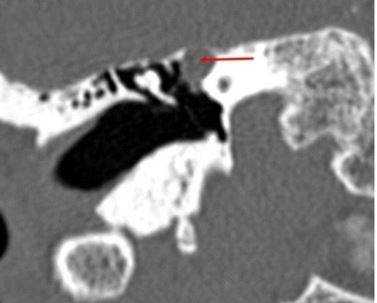

Шваннома лицевого нерва: осевое КТ-изображение (костное окно) демонстрирует расширение ганглия, присутствует однородная масса мягких тканей (стрелка)